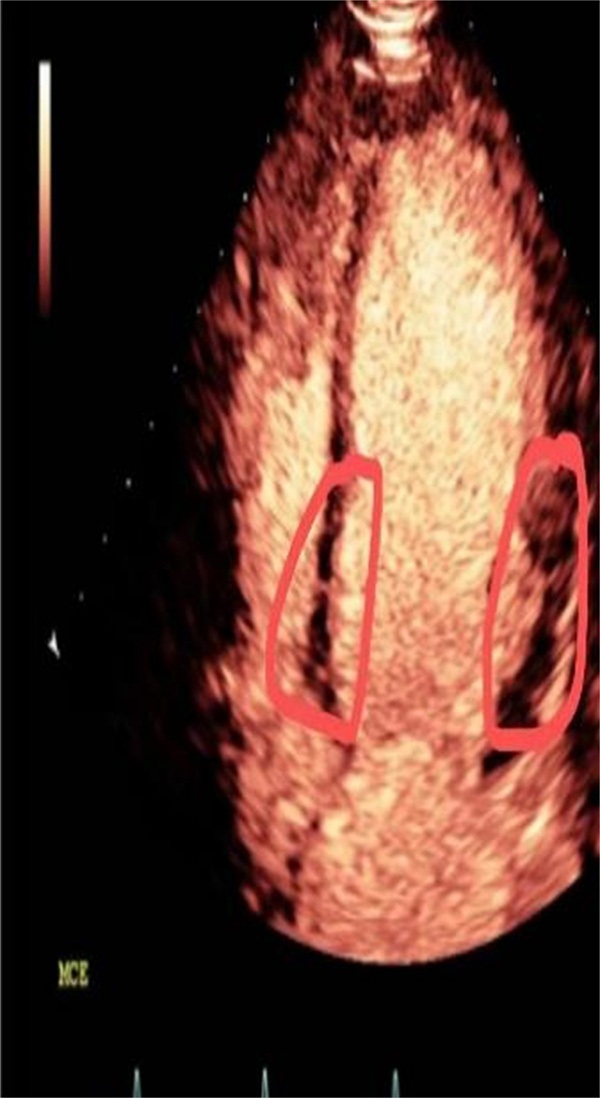

2022年也是超声心动全面发展的一年,2022年1月至今,心内科开展了心脏超声造影,包括左心腔超声造影、左心肌超声造影和右心超声造影,顺利完成了左心室血栓评估、心尖肥厚性心肌病、心肌致密化不全、PCI手术患者术前、术后心肌灌注评估、透析患者心肌的评估。

心脏超声造影通过外周静脉注射超声造影剂(ultrasound contrast agent,UCA),实时动态且更清晰地观察心肌灌注及心腔,反映心脏结构、功能及其冠脉微循环。

定量评价左室容量、射血分数、节段性运动异常(与核素显象、磁共振有良好的相关性),观测心脏内部细微解剖结构(左室心尖肥厚、心肌致密化不全、心尖血栓、心尖室壁瘤),能更清晰的显示左心房的解剖特征,尤其是左心耳,对鉴别血栓、伪像、明显自发显影和左心耳正常解剖结构有很大帮助。